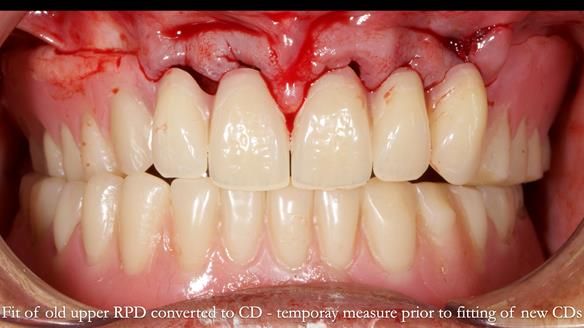

Welcome to Newsletter 62. In this edition, I walk through the process of removing 5 upper anterior teeth, adding to an existing upper RPD, followed by creating and fitting metal based complete dentures for Rafique, a 71 year old man.

The detailed clinical situation and treatment process are outlined below, with clinical work provided by me and technical work by Rowan Garstang. The treatment spanned 12 months, involving removing 5 upper anterior teeth, adding to an existing upper RPD, followed by creating and fitting metal based complete dentures.